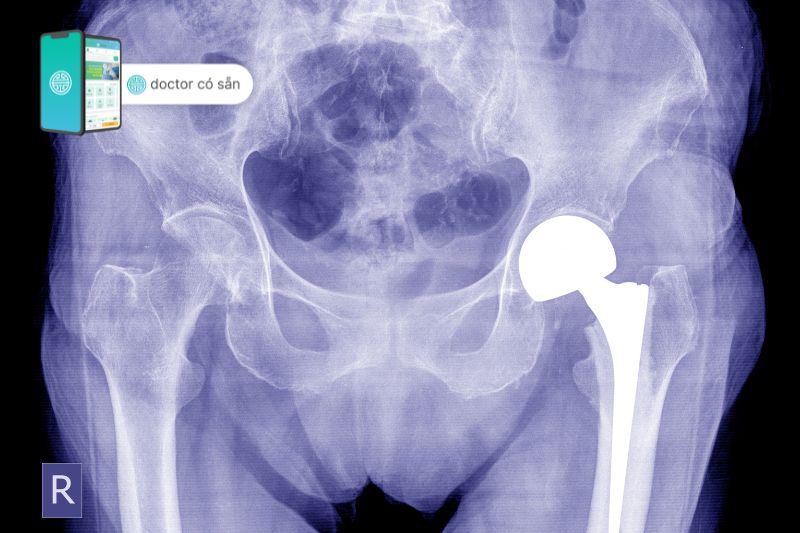

Phẫu thuật thay khớp háng là một phương pháp phẫu thuật trong đó bác sĩ loại bỏ các bộ phận bị tổn thương của khớp háng và thay thế bằng khớp nhân tạo mới. Những bộ phận nhân tạo này bắt chước chức năng của khớp háng bình thường và được chia thành 2 loại là thay khớp háng toàn phần và bán phần.

Thay khớp háng toàn phần

Phương pháp này thay thế cả hai thành phần là chỏm xương đùi và ổ cối của xương chậu. Sau khi hoàn thành, các bộ phận khớp hoạt động liền mạch với nhau giúp chuyển động cải thiện đáng kể. Những bệnh nhân cần thực hiện phẫu thuật thay khớp háng toàn phần thường bị viêm xương khớp từ trung bình đến nặng, viêm khớp dạng thấp hoặc các tổn thương khớp háng nghiêm trọng.

Thay khớp háng bán phần

Thay khớp háng bán phần là phẫu thuật ít xâm lấn hơn, thay thế chỉ chỏm xương đùi và giữ nguyên ổ khớp háng của người bệnh. Thông thường, những bệnh nhân phù hợp với phương pháp này là những bệnh nhân có tổn thương xương hông, khớp háng và ổ xương chậu vẫn còn khỏe mạnh. Thay khớp háng bán phần gồm 2 loại:

Có 2 loại thay khớp háng bán phần bao gồm:

- Phẫu thuật thay khớp háng bán phần đơn cực

Bao gồm một đầu chỏm Austin Moore được gắn chắc chắn vào thân chuôi xương đùi. Việc thay khớp háng đơn cực hiếm khi được thực hiện và hầu hết đều là phẫu thuật lưỡng cực.

- Phẫu thuật thay khớp háng bán phần lưỡng cực

Trong phẫu thuật thay khớp háng lưỡng cực, đầu chỏm Bipolar của xương đùi bao gồm 2 khối cầu. Một khối cầu kim loại nhỏ quay tròn bên trong khối cầu kim loại lớn được phủ ở giữa bởi 1 lớp đệm nhựa polyetylen giúp bề mặt quay được trơn tru, hạn chế tình trạng ma sát. Thiết kế lưỡng cực mang lại sự ổn định, chuyển động cao hơn và cũng giúp bảo vệ sụn khớp.

Quá trình phẫu thuật

Phẫu thuật thay khớp háng bán phần có thể sẽ gây mê toàn thân hoặc lựa chọn gây tê tủy sống, gồm 4 bước:

- Bước 1: Thực hiện vết mổ ở bên hông (cách tiếp cận sau) hoặc vết mổ ở phía trước hông (cách tiếp cận trước) đến khi nhìn thấy khớp.

- Bước 2: Bác sĩ cẩn thận loại bỏ phần bị tổn thương của khớp háng, thường là đầu trên của xương đùi và giữ lại phần ổ cối nguyên vẹn.

- Bước 3: Phần xương đùi sẽ được tạo hình lại và lấp khớp nhân tạo mới vào.

- Bước 4: Vết mổ được đóng lại bằng chỉ khâu hoặc ghim cùng với băng vô trùng.